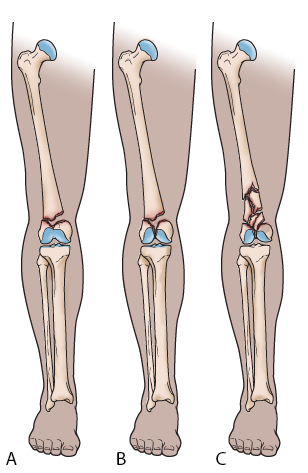

Different types of distal femur fractures

(Left) A transverse fracture across the distal femur.

(Center) An intra-articular fracture that extends into the knee joint.

(Right) A comminuted fracture that extends into the knee joint and upwards into the femoral shaft.

Distal femur fractures can be:

• Closed — meaning the skin is intact (not broken).

• Open — an open fracture is when a bone breaks in such a way that bone fragments stick out through the skin or a wound penetrates down to the broken bone. Open fractures often involve much more damage to the surrounding muscles, tendons, and ligaments. They have a higher risk of complications and take a longer time to heal.

When the distal femur breaks, both the hamstrings and quadriceps muscles tend to contract and shorten. When this happens the bone fragments change position and become difficult to line up with a cast.

Distal femur fracture in which the bones are out of alignment

In this X-ray of the knee taken from the side, the muscles at the front and back of the thigh have shortened and pulled the broken pieces of bone out of alignment.